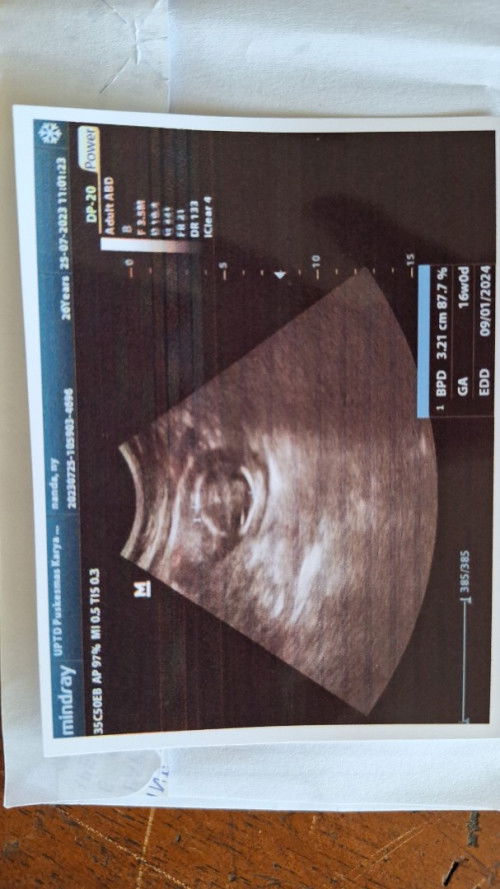

Maaf bunda, mau nanya,ini gmn ya, td saya USG UK 16W janin aktif bergerak namun DJJ lemah.

Itu kenapa ya bund? Apakah berbahaya?

dokter spog jelasin gimana bun kok bisa djj lemah tapi janinnya aktif? kalau bilang bahaya atau nggak? pastinya bahaya